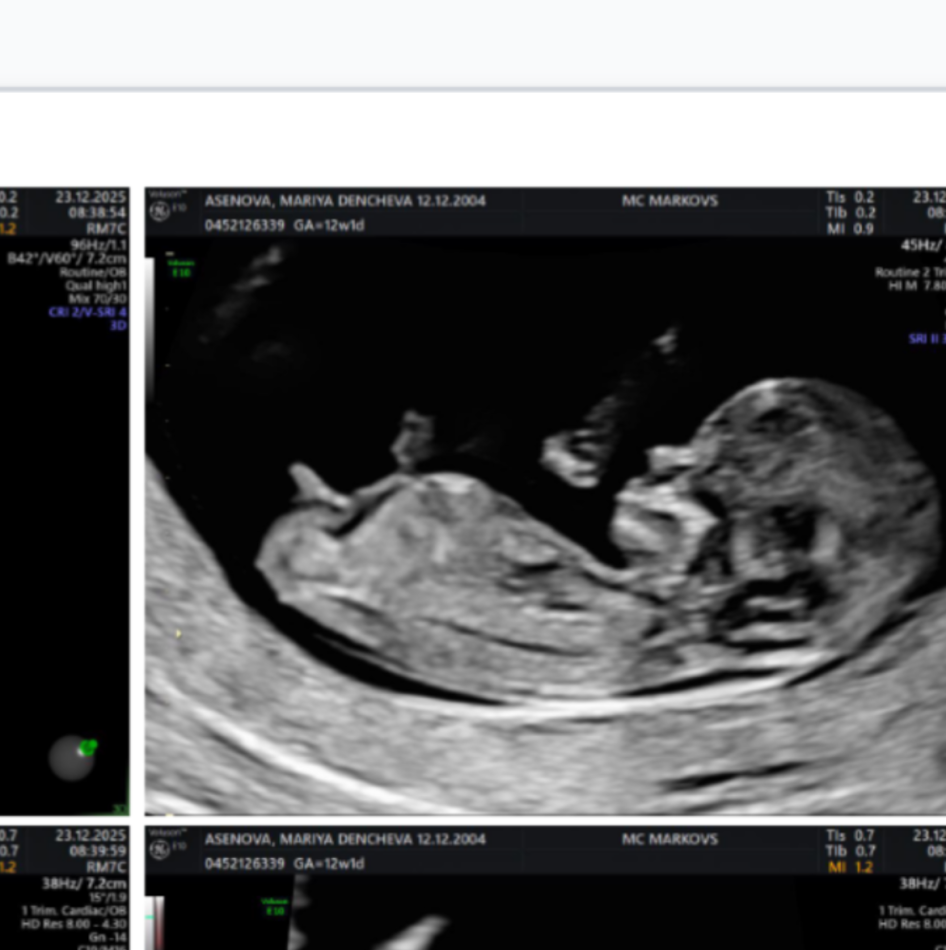

Според вас момче или момиче е казаха най-вероятно момче🙂

Момченцее😇 Nub - ът е на горе клони към 360°❤️🙂